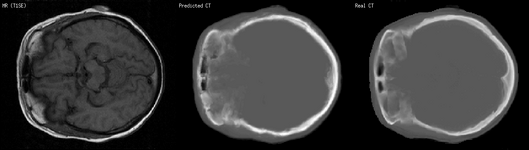

Converting medical scans (Magnetic Resonance scans are transformed into Computed Tomography scans) |